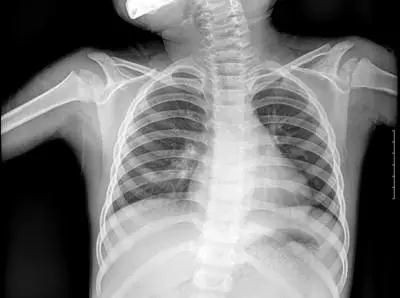

▲X射線成像圖

骨骼、鈣化灶、體內液體等(聽起來質地較厚重的組織),吸收X光較多,因此形成白色影像,也就是傳說中的“高密度影”,上圖的上臂、肋骨就是如此。呼吸道、胃腸道、脂肪組織(聽起來質地較疏松),吸收X光較少,在片子上呈現黑色影像,即“低密度影”,圖中含氣體較多的肺臟是代表。再就是密度居中的實質器官、肌肉、結締組織,比如心臟,在片子上呈現的影像介于黑白兩色之間。X光片“涇渭分明”的特點幫醫生辨別身體的不同病變。骨折、肋骨病變,密度高的骨骼白色影像哪里出問題一目了然,比如液氣胸等肺部及氣道病變,肺臟的黑色影像中就會混入明亮的白色。